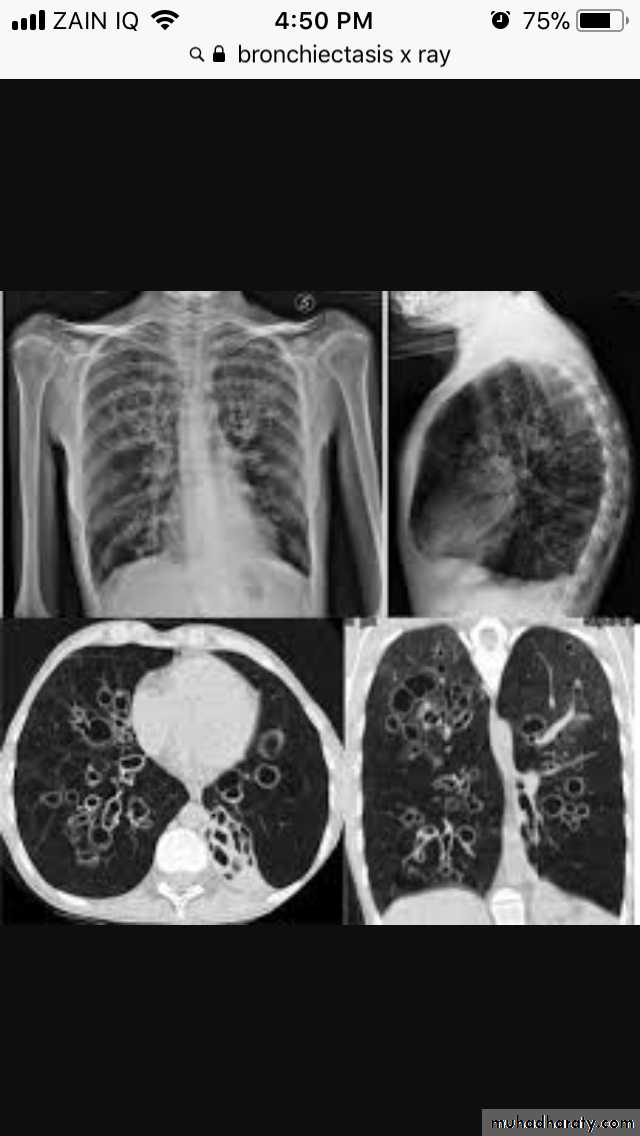

Bronchectasis

Abnormal irreversible dilatation of bronchioles with thickening of their walls . Presented with recurrent pneumonias & haemoptysis ..Types:Cystic

Fusiform

Cylendrical

In which the bronchiole is wider than the near by vascular branch

Causes –infancy & childhood infection

-TB

-pulmonary fibrosis

-cystic fibrosis

-immotile cilia syndromes